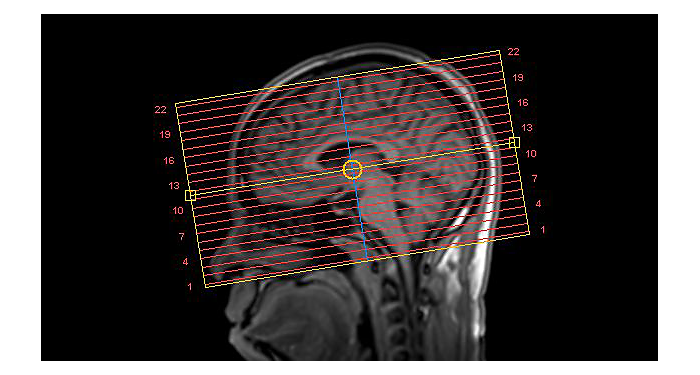

70% of radiologists consider neuro indications to be challenging, mostly due to a lack of appropriate imaging and visualization techniques¹. Philips aims to provide the best possible diagnostic clarity and treatment guidance for all patients with neurological disorders. By leveraging our dStream digital platform, this year, we are introducing, a set of novel imaging and visualization strategies. These may empower you to resolve complex neuro questions with more certainty, as well as unlock new neuro territories in advanced Neurofunctional applications. This is a key step towards elevating neuro diagnostics and ultimately touching more lives with MR imaging. ¹ TMTG Market Survey 2016

New neuro applications